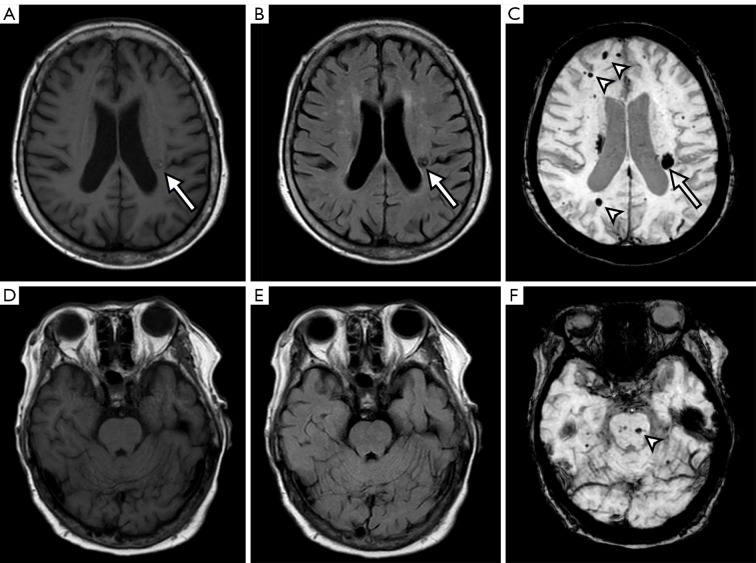

Late-onset familial cerebral cavernous malformation without a family history: a case description.